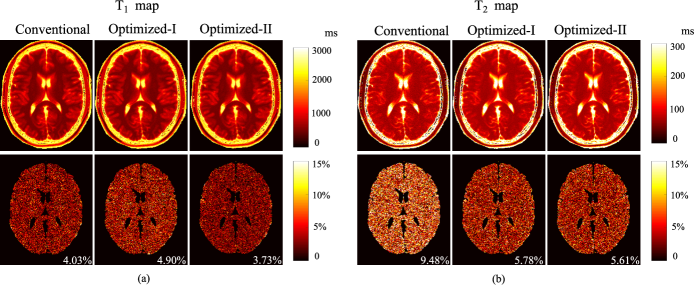

Refer to caption

Figure 1: Ground truth parameter maps for the brain phantom: (a) T1subscript𝑇1T_{1} map, (b) T2subscript𝑇2T_{2} map, and (c) M0subscript𝑀0M_{0} map. Note that the two ROIs (respectively in the white matter and gray matter) are marked in (a).

We created a numerical brain phantom to simulate single-channel MR fingerprinting experiments. We took the T1subscript𝑇1T_{1}, T2subscript𝑇2T_{2}, and M0subscript𝑀0M_{0} maps from the Brainweb database [48] as the ground truth, as shown in Fig. 1. We set the experimental field-of-view (FOV) as 300×300mm2300300superscriptmm2300\times 300~{}\mathrm{mm}^{2}, and the matrix size as 256×256256256256\times 256. We simulated MR fingerprinting experiments with the IR-FISP sequence [15], which is robust to main magnetic field inhomogeneity. Moreover, for simplicity, we assumed that the transmit RF field was homogeneous in the simulations.

Figure 5: Reconstructed parameter maps from the fully-sampled MR fingerprinting experiments (N=400𝑁400N=400 and SNR=33dBSNR33dB\mathrm{SNR}=33~{}\mathrm{dB}), using the acquisition parameters from the conventional scheme, Optimized-I, and Optimized-II. (a) Reconstructed T1subscript𝑇1T_{1} maps and associated relative error maps. (b) Reconstructed T2subscript𝑇2T_{2} maps and associated relative error maps. Note that the overall error is labeled at the lower right corner of each error map, and the regions associated with the background, skull, scalp, and CSF were set to be zero.